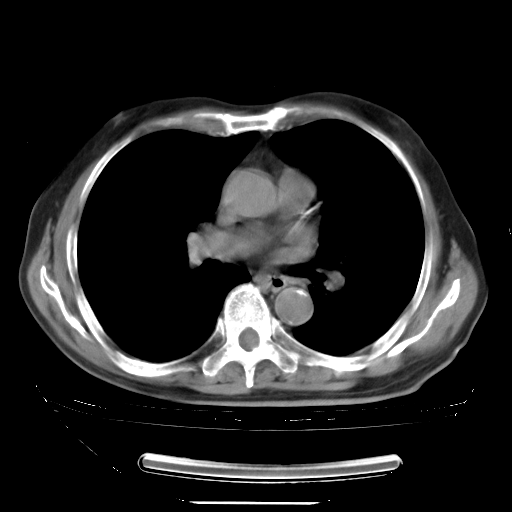

胸腹部CT,诊断意见:左上肺叶钙化灶、左侧胸膜局限性增厚并钙化、胆囊炎。描述部分肺组织呈磨玻璃样改变。